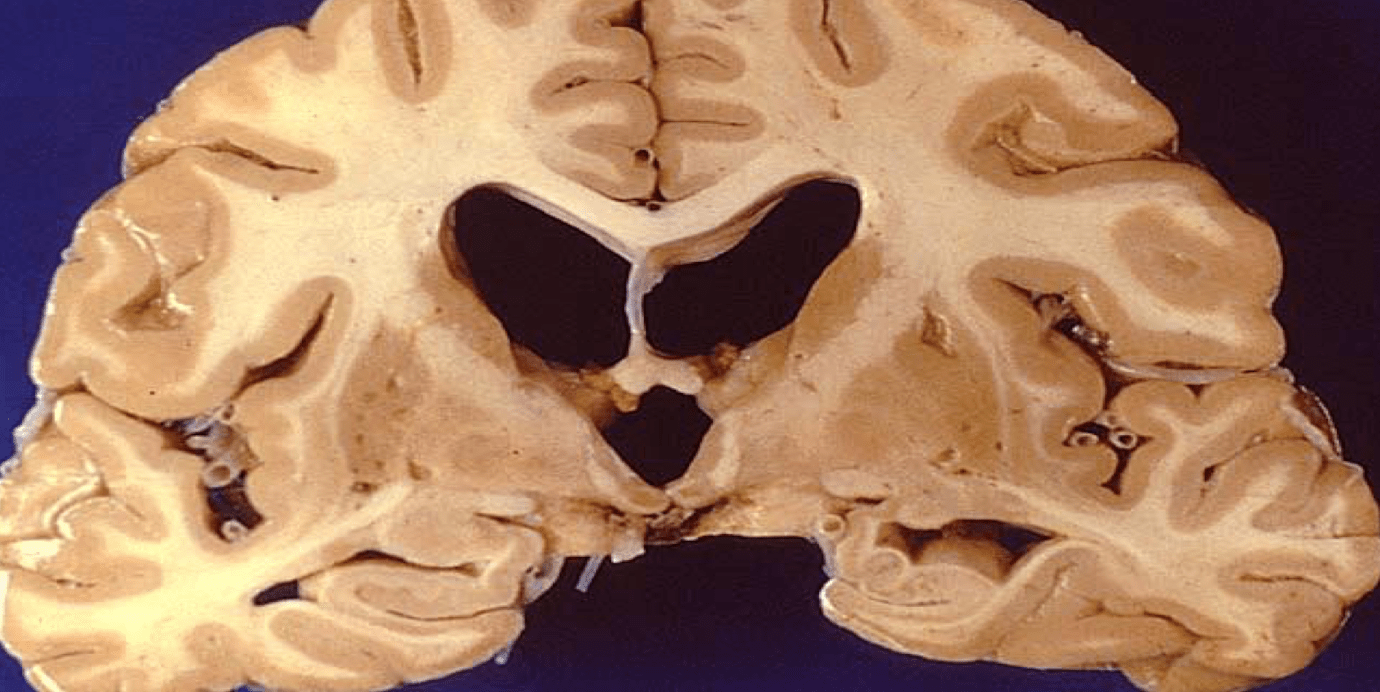

this enlargement of both the lateral and third ventricle suggests what pathology

hydrocephalus of some sort

**in this case specifically normal pressure hydrocephalus